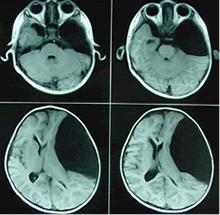

蛛網膜囊腫術前(左)術後(右)對比蛛網膜囊腫患者的最佳治療方案仍有許多爭論。有觀點認為當患者無顱內高壓症狀或無神經系統定位損害時應保守治療,因為有部分患者在行手術探察或切除術後出現不能預知的惡化或死亡。主要是囊腫過份急速減壓使腦組織移位或出現術後感染、出血等嚴重併發症。也有觀點認為即使無症狀患者手術治療可以減少微小損傷導致硬膜下血腫的機率,兒童在無症狀時手術治療可以解除腦葉發育不全,腦組織代謝異常等囊腫對腦功能潛在的影響。當囊腫不斷增大引起顱壓增高或與之相關的腦積水、硬膜下血腫、神經定位損害、與囊腫相關癲癇發作,影像學提示腦組織壓迫時應考慮手術治療。手術治療的目的是解除壓迫。

蛛網膜囊腫2、安裝分流裝置行囊腫分流術。因為囊壁具有分泌功能,所以完全切除囊壁是最合理的方法。但是囊壁與周圍神經組織粘連緊密,所以完全切除很少能夠做到。在很多病例中廣泛但不徹底的切除囊壁或開放囊腔可以充分緩解臨床症狀,術後隨訪行CT檢查可見囊腫體積減小或消失。有報導直接切除囊壁手術的失敗率達25%,高復發率與囊壁切除不足、囊腫開口閉塞、或蛛網膜下腔腦脊液吸收不充分有關。囊腔分流術的優勢是技術成熟可靠,即使在嬰幼兒患者治療中死亡率也很低,可使腦脊液緩慢減少,避免腦組織劇烈移位產生嚴重後果,不足是囊腫復發率高,有報導可達50 %。